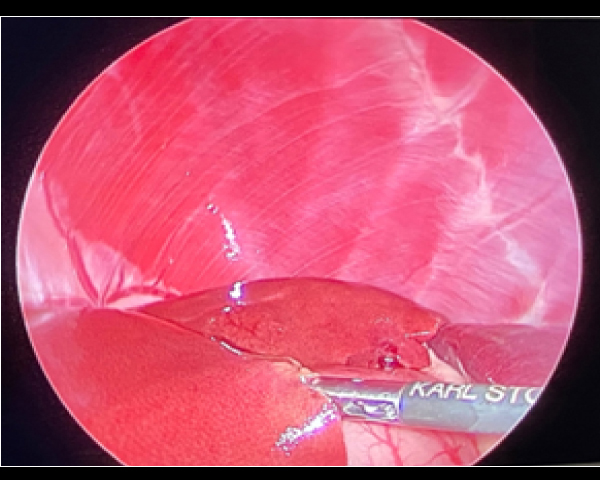

腹腔鏡を用いた副腎腫瘍摘出術